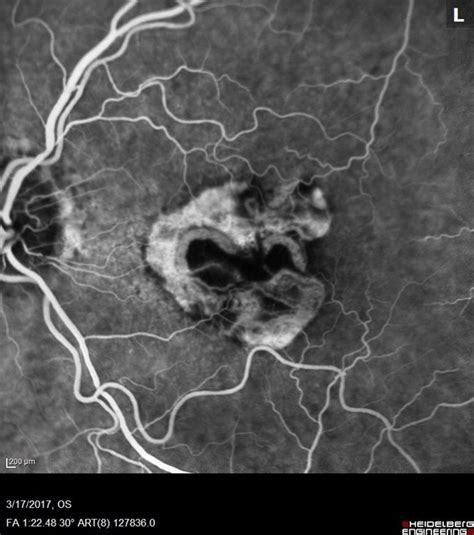

Now, let’s talk about active CNV . CNV, or choroidal neovascularization, is the growth of these abnormal blood vessels. CNV is a major feature of wet AMD. The choroid is a layer of blood vessels located beneath the retina. When CNV develops, these blood vessels grow from the choroid through a membrane called Bruch’s membrane and into the space under the macula. They are fragile and prone to leakage. When these blood vessels leak, it causes fluid and blood to accumulate under the macula. This can lead to swelling, distortion of vision, and vision loss. The term “active” in active CNV means that these blood vessels are currently growing and leaking, causing ongoing damage to the macula. In other words, the disease is actively progressing. The activity of CNV is assessed through imaging tests like optical coherence tomography (OCT) and fluorescein angiography (FA). These tests help doctors determine if the CNV is active and how it’s affecting the macula. Managing active CNV is the cornerstone of treating wet AMD. That’s why prompt diagnosis and treatment are crucial to protect your eyesight. Treatments aim to stop the growth and leakage of these blood vessels, preventing further damage to the macula.

Alright, let’s talk about spotting the signs of neovascular AMD with active CNV . Recognizing the symptoms and getting a prompt diagnosis is super important. Early symptoms of wet AMD can be subtle at first, so it’s essential to pay attention to any changes in your vision. Common symptoms include: * Distorted vision: Straight lines may appear wavy or bent. This is a classic symptom of wet AMD. * Blurry vision: Difficulty seeing fine details, like when reading or driving. * Dark or empty areas: A blind spot or a dark area in the center of your vision. * Changes in color perception: Colors may appear less vibrant or washed out. * Sudden vision changes: Any sudden worsening of your vision should be investigated immediately. If you experience any of these symptoms, it’s crucial to see an eye doctor as soon as possible. Your eye doctor will perform a comprehensive eye exam to diagnose wet AMD with active CNV. The exam usually includes: * Visual acuity test: Measures how well you can see at different distances. * Dilated eye exam: Your pupils are dilated to allow the doctor to examine the retina and macula. * Optical coherence tomography (OCT): This imaging test provides detailed cross-sectional images of the retina, allowing the doctor to see the CNV and any fluid or swelling. * Fluorescein angiography (FA): A dye is injected into your arm, and special photographs are taken to visualize the blood vessels in your retina and detect any leakage from the CNV. These diagnostic tests are essential for confirming the diagnosis and assessing the activity of the CNV. Early detection and diagnosis are vital because the earlier the treatment is started, the better the chances of preserving your vision. Regular eye exams are especially important for people over 50 and those with risk factors for AMD, such as a family history of the disease.